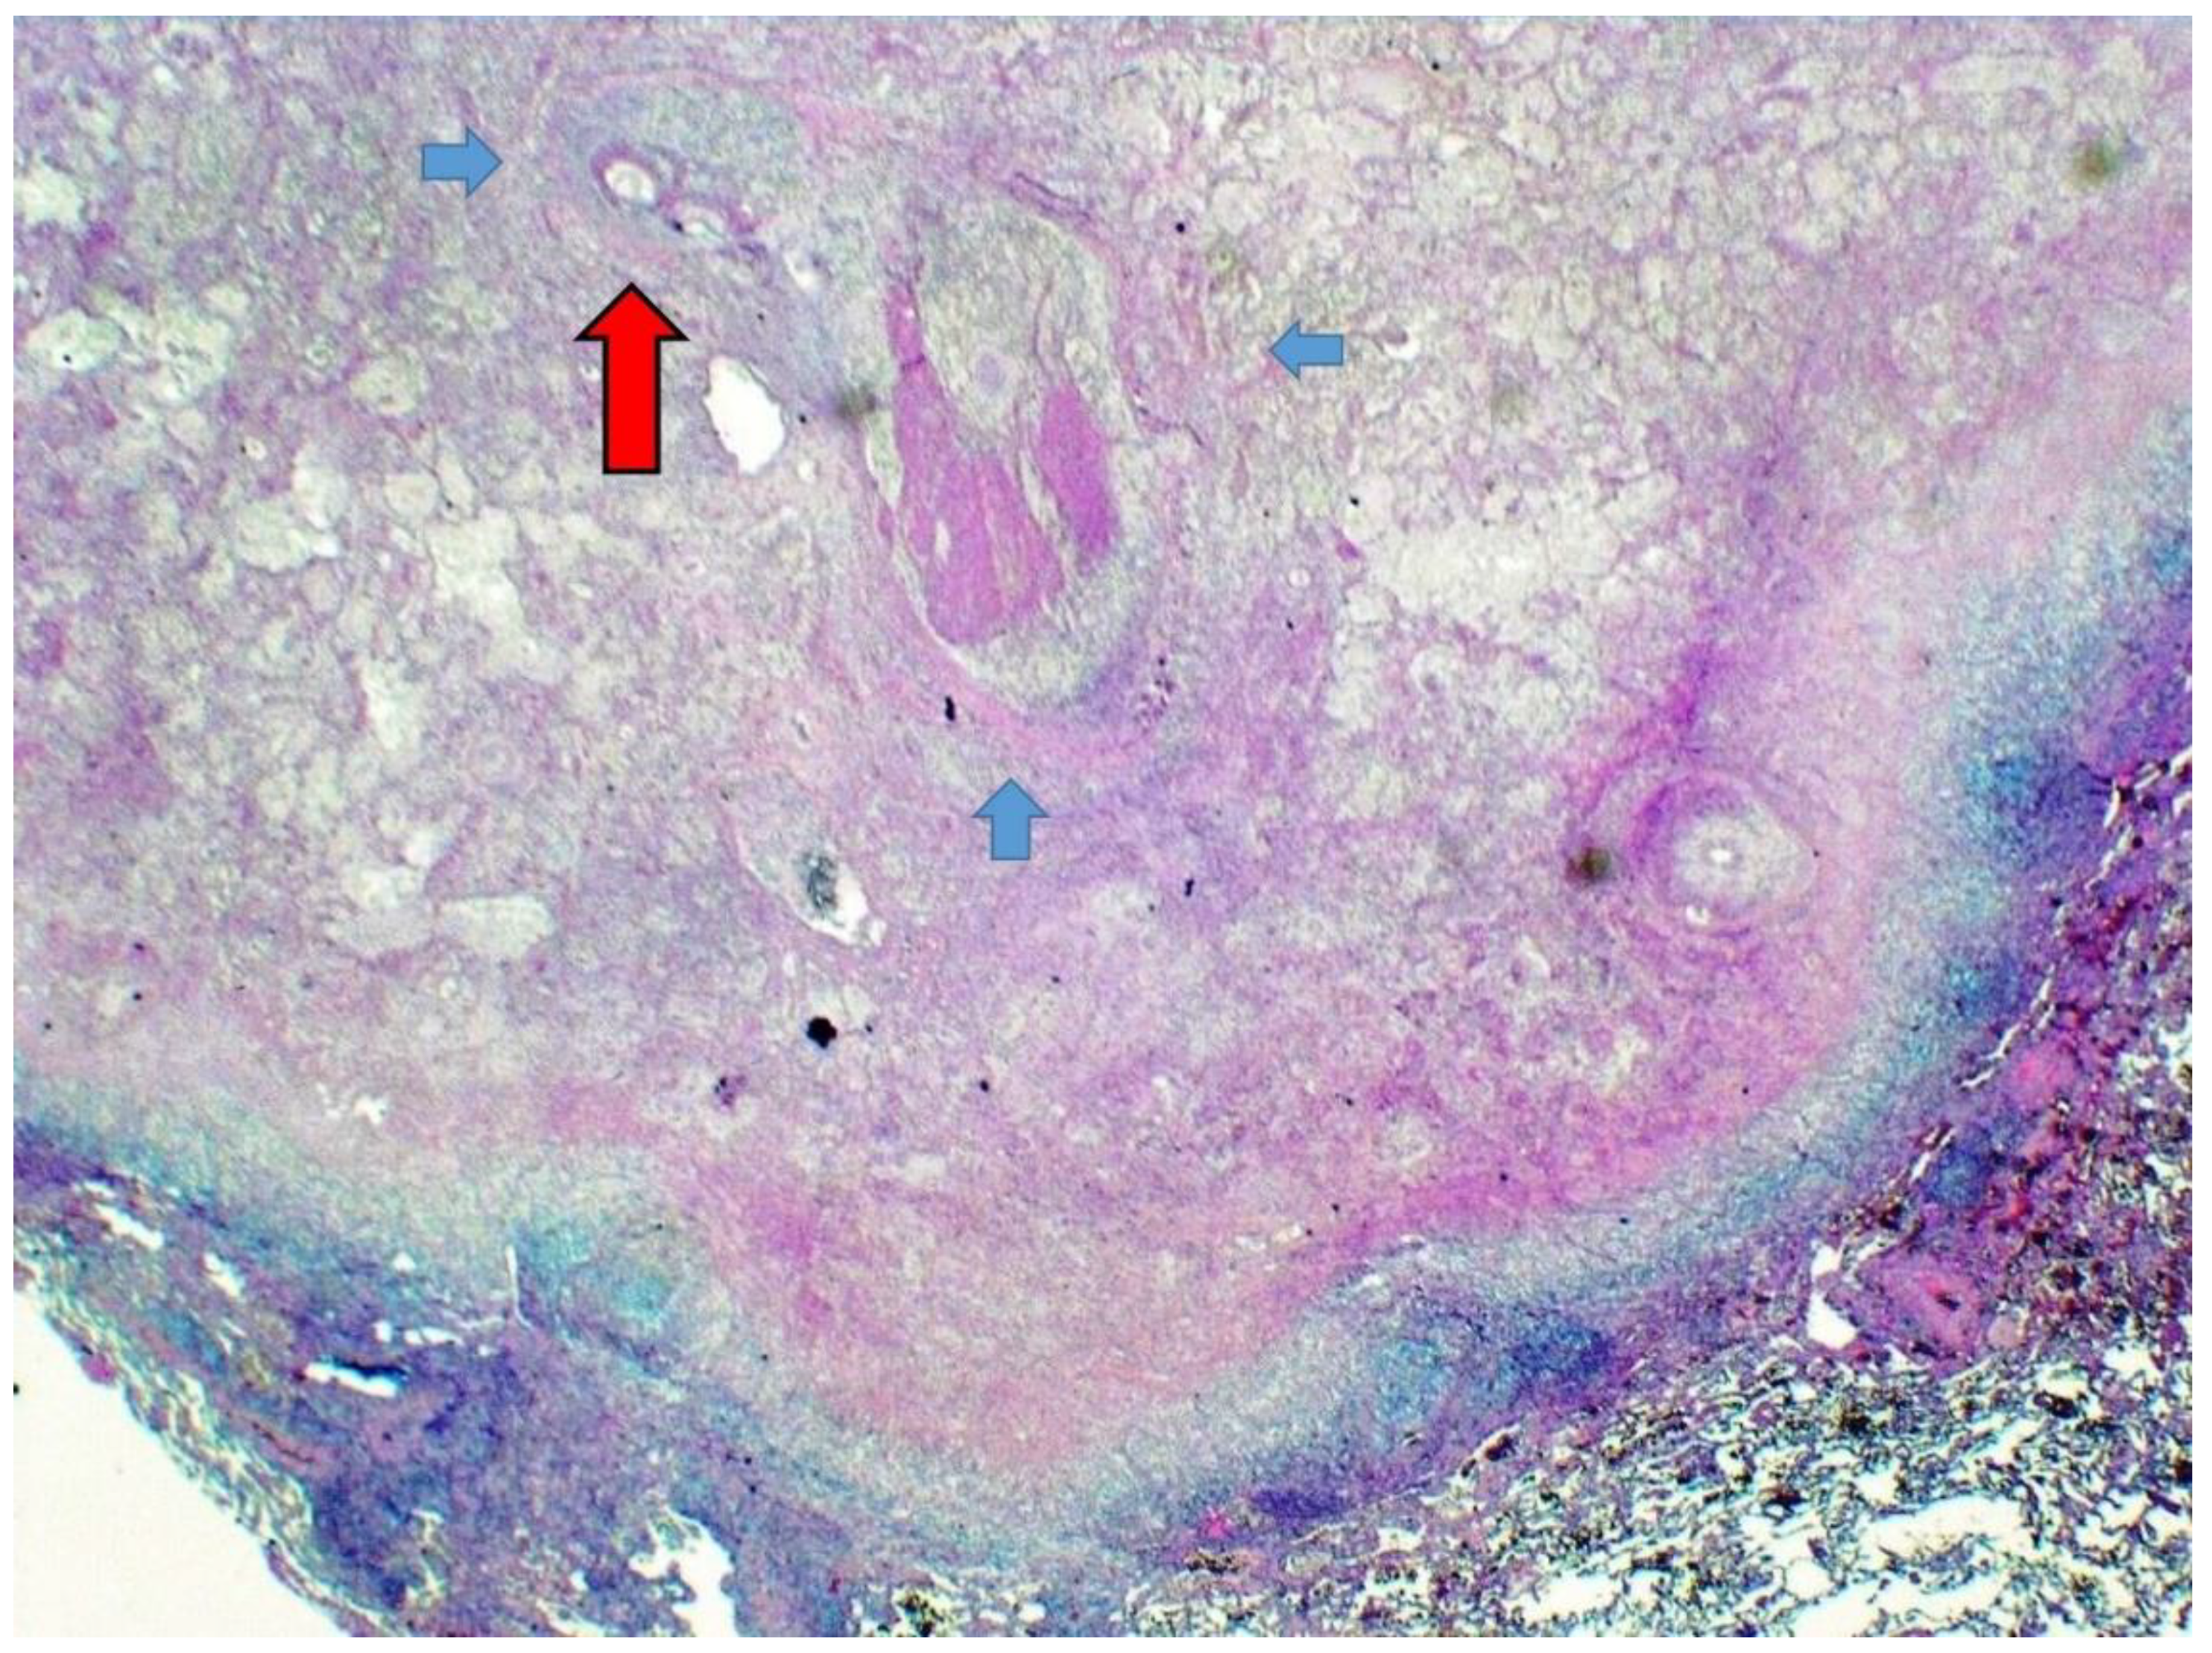

3.1. Case Report